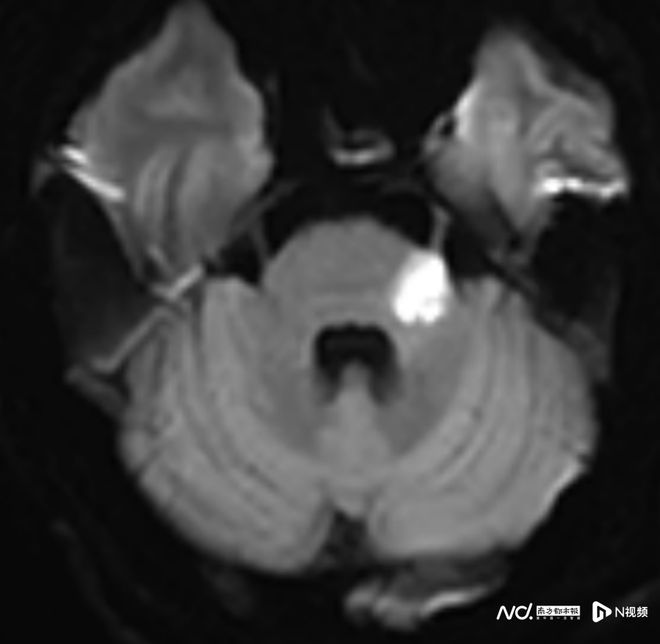

相反,59歲的趙叔在冠脈支架術后出現頭暈、行走不穩,卻拖延至十天后因摔倒才就醫,錯過了最佳治療窗口,最終留下行走不穩的后遺癥,需長期康復。

卒中發病呈現年輕化趨勢這個放松動作可能“按”出腦卒中(圖5)